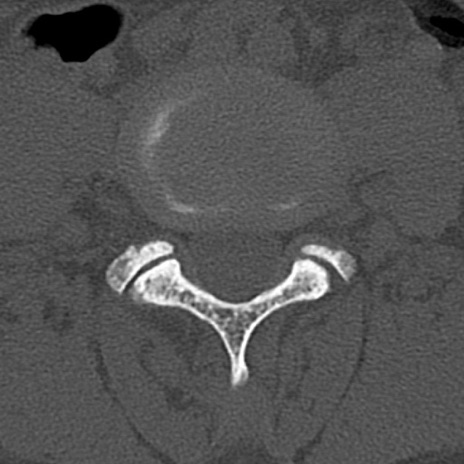

腰椎CT

横断像と矢状断像